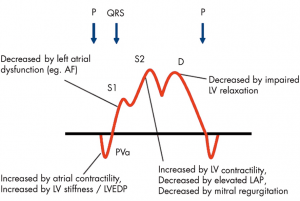

そもそも以前は左室拡張能障害の指標としてPV flowは使用されてきました。下の図は専門外でも皆様どこかでみたことある図ではないでしょうか。[3]四段目がPV flowです。左房の入り口の波形ですから、左房圧を反映して波形が変化するのは理解しやすい部分だと思います。

(文献[3]より引用: Doppler法による拡張能評価基準)

(文献[3]より引用: Doppler法による拡張能評価基準)

ただ、PV flowの問題点は様々な指標を含んでしまっているがためにそれだけでは何を表現しているかわからない、というのが複雑な点です。ざっと挙げるだけでも左房コンプライアンス、左室/左房の収縮/拡張能、測定時の血行動態、そして僧帽弁逆流などの要素が関わってきます。

(文献[4]より引用: PV波形に関連する因子)

(文献[4]より引用: PV波形に関連する因子)